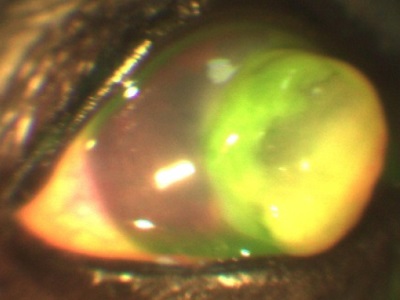

Atunci când diferite defecte ale corneei (eroziune, ulcer, traumatisme), creează edem, îngroșarea corneei, datorită cărora devine alb (opac).

eroziunea corneei, iepure

defecte corneene apar, atât din cauza traumei de factori externi, și fără ele. Genele patologici, pleoape volvulus (parțială și completă), keratoconjunctivita sicca, toate acestea conduc la o leziune a corneei (eroziuni ale corneei sau ulcere).

Este important să distingem aceste stări patologice, ca și tratamentul eroziuni, ulcere și leziuni datorate diferitelor motive diferite. Oftalmolog specialist cu experiență suficientă și echipament specializat pentru a ajuta la identificarea bolii, și cauza algoritmului de acțiune.